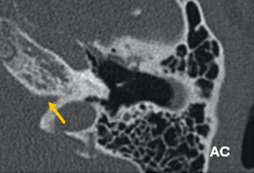

Figura 5. Ventana oval obliterativa de oído derecho en un corte coronal de oído medio |

El estado de la ventana redonda es importante, ya que su afectación se asocia a un mayor riesgo de hipoacusia neurosensorial posquirúrgica. La obliteración de la ventana redonda, aunque no se frecuente, puede diagnósticarse preoperatoramiente y podría contraindicar el tratamiento quirúrgico (Fig.6).

Figura 6. Oídos derechos con obliteración de ventana redonda (flecha amarilla) |